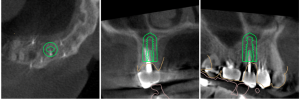

This video demonstrates a fully guided immediate implant placement protocol following premolar extraction, combined with immediate provisional restoration. The case highlights a digitally driven workflow designed to enhance accuracy, efficiency, and prosthetically guided implant positioning.

Step-by-step, the procedure covers atraumatic tooth extraction, guided implant placement using a surgical guide, and chairside fabrication and delivery of an immediate provisional restoration. Clinical considerations for achieving primary stability, soft tissue preservation, and optimal emergence profile are emphasized to support predictable esthetic and functional outcomes.

- Digital planning and fully guided surgical execution

- Techniques for atraumatic extraction and implant site preparation